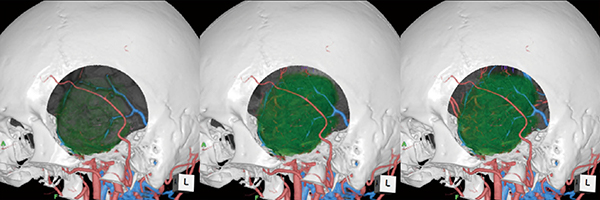

脳神経外科の脳腫瘍術前精査では、必ずCTとMRIを施行し、CT perfusionでは脳腫瘍と栄養血管の位置関係と血流動態を把握することを目的とする。MRIではtractography、3D-FLAIR、MR DSA、MR perfusionを撮像し、脳腫瘍と神経線維の位置関係および血流動態を把握することを目的としている。CTでは動脈・静脈を個々に抽出し、MRIでは腫瘍抽出、tractographyによる錐体路の描出をする。これらをFusionすることで、血管と腫瘍および神経線維の情報を任意の方向から作成することが可能となる(図2)。CTの頭蓋骨の画像と3D-FLAIRの脳表画像をFusionし、頭蓋骨の透過度を変化させることで、脳実質内の腫瘍の位置や手術時のアプローチなどを決定する際の有用な情報となる(図3)。

さらに、手術時の開頭野を想定し、頭蓋骨を取り除き脳表のみ切り込んでいくことで、脳表から腫瘍までの距離、腫瘍の栄養血管や錐体路の位置関係の把握ができ、術前のシミュレーションに役立つ(図4)。

図2 動脈・静脈・腫瘍・椎体路のFusion画像

図4 術前シミュレーション画像